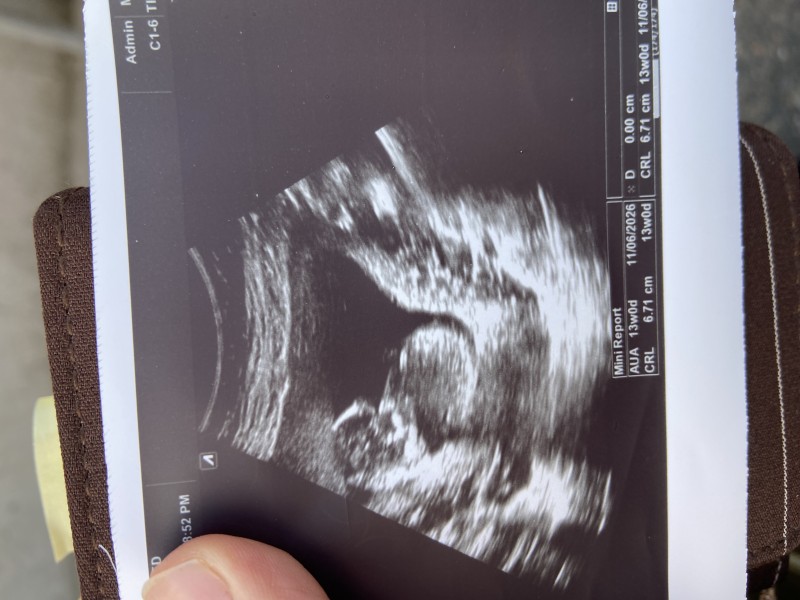

Tahminde bulunur musunuz kızlar

Kızlar tahminde bulunur musunuz 🩷💕

Başlıktaki soruya cevap veriyorum; pipi değil belki kordondur demek %50 kız demek

Benim de kafam çok karıştı oğlumda bu haftaydı yüzde yüz erkek dedi aynı doktor ama bunda böyle dedi ama erkek bence dedi anlamadım oda tam emin olamadı

Tam bu şekil erkek dedi doktor ama pipi degıl kordon da olabilir dedi 15. Haftadaydık, sonra da yokk yok erkek dedi gönderdi 16da kızım oldugunu ögrendım😂